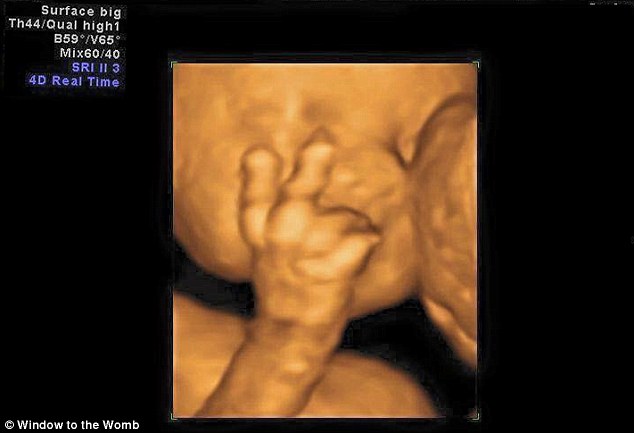

Aimee Ford è andata a fare un’ecografia al settimo mese di gravidanza insieme al marito Russ Worlock. I due hanno raccontato di essere rimasti completamente scioccati dopo aver visto il loro terzo figlio che saluta mostrando due dita vicino al volto. I due hanno raccontato di aver riso: “La nostra ecografia del settimo mese di gravidanza, resterà per sempre indimenticabile. Io proprio non me l’aspettavo” ha detto la donna già madre di due figli: Evelyn che ha 4 anni e che ha partecipato all’ecografia, ed Edward nato nel mese di novembre.

Il feto che saluta la mamma con due dita6